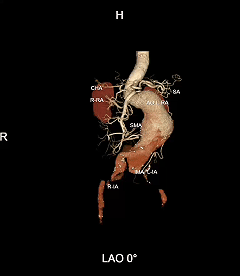

现病史:患者8小时前无明显诱因下出现头晕伴恶心呕吐,呕吐物为胃内容物,无视物旋转,无呕血黑便,无胸闷气促,无胸痛,遂至当地医院就诊查。CTA提示主动脉瘤,腹主动脉多发钙化,胸主动脉多发钙化斑块。

IV型胸腹主动脉瘤,瘤颈和双侧髂动脉严重扭曲,瘤体巨大,内脏分支血管开口角度倾斜

采用G-Branch胸腹主动脉覆膜支架隔绝瘤体,重建内脏区分支。主体使用TAAA3418120e7i1010,腹腔干和肠系膜上动脉分别植入直径10mm覆膜支架,右肾直径6mm支架,左肾直径7mm支架

G-Branch在本例手术中展现出对扭曲解剖结构的出色适应性,针对该患者严重扭曲的瘤颈,支架系统的优异柔顺性使其能够顺利通过复杂路径,完成内脏分支血管的重建。

其独特的双内嵌、双外翻混合多分支设计兼顾了操作效率与结构可靠性,预置导丝系统简化了肠系膜上动脉(SMA)和腹腔干动脉(CA)的超选流程,显著提高手术效率。